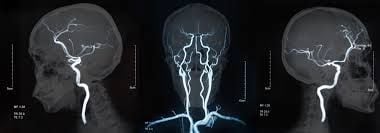

[기타]CT 촬영 경험자들은 대부분 불쾌했다고 응답하는 것...jpg 작성자JB|작성시간25.12.22|조회수37,453 목록 댓글 2 글자크기 작게가 글자크기 크게가 https://theqoo.net/square/4036711194조영제 정맥투여화한느낌 + 메스꺼움 발생 함※메스꺼움 같은 부작용 없는 사람도 있음 다음검색 현재 게시글 추가 기능 열기 북마크 공유하기 신고 센터로 신고 댓글 댓글 2 댓글쓰기 답글쓰기 댓글 리스트 작성자JB | 작성시간 25.12.22 나는 뇌 찍었는데 올라오는 느낌이 느껴짐 다신 안찍고싶어 작성자JB | 작성시간 25.12.22 난 걍 뜨거웟음 댓글 전체보기